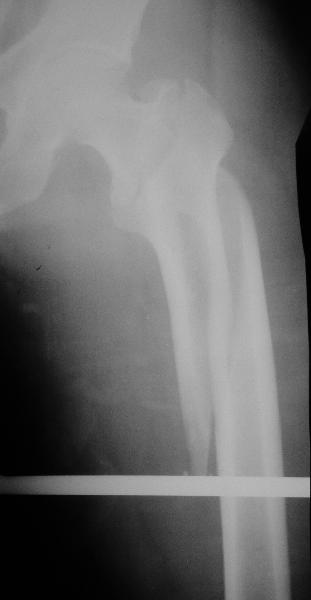

Как раз недавно у меня был примерный случай: больному 36 лет, поступил ночью, травма в результате мотоциклетной аварии, кроме чрезвертельного и спирального перелома левого бедра имеется переломы костей предплечья с этой же стороны. Скелетное вытяжение, а на следующий день больной про оперирован на ортопедическом столе с дистракцией. Чтобы не расколоть чрезвертельный перелом провели временную спицу ближе к переднему кортексу, из малого разреза костодержатель для репозиции, а фиксацию провели антиградным штифтом. Этапы операции на снимках.

Да, сейчас это и у нас самый напрашивающийся выбор. Сделали гвоздем ChM, картинки в приложении.